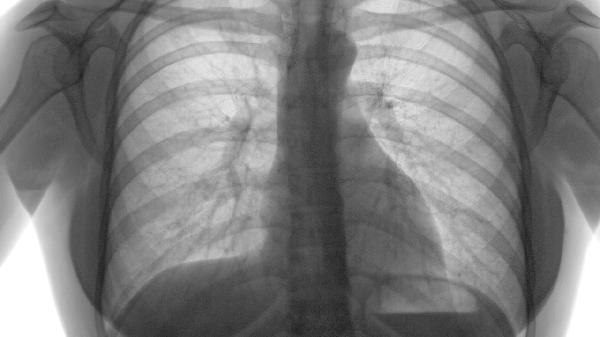

典型桶狀胸表現(xiàn)為前后徑增大、肋間隙增寬,叩診呈過清音。這是肺過度充氣使膈肌下移、胸廓持續(xù)擴(kuò)張的結(jié)果。呼吸時(shí)胸廓運(yùn)動(dòng)幅度減弱,聽診呼吸音普遍減低。